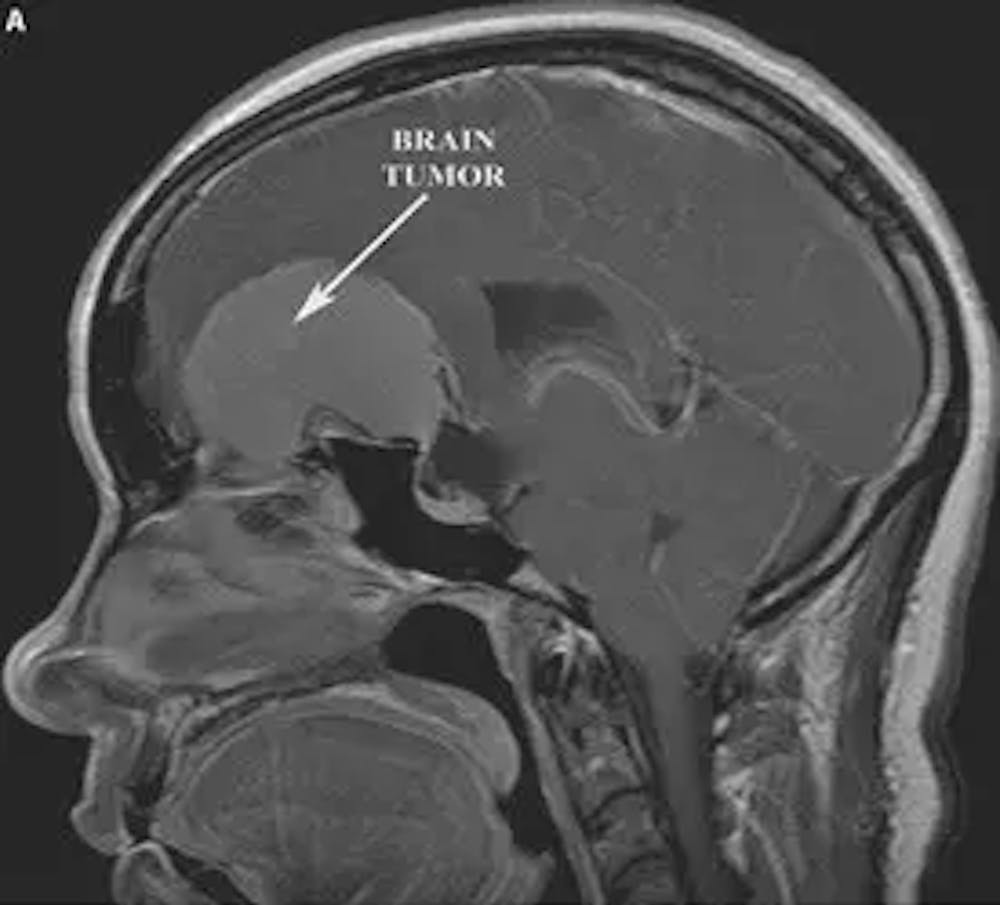

એ) પ્રિ-ઓપરેટિવ સગિટલ T1 એમઆરઆઈ કોન્ટ્રાસ્ટ સાથે આગળના લોબને સંકુચિત કરતા મોટા મેનિન્જિયોમા દર્શાવે છે

બી) પોસ્ટ-ઓપરેટિવ સગિટલ T1 એમઆરઆઈ રિસેક્શન કેવિટી અને આગળના લોબ્સ પર સામૂહિક અસરનું રિઝોલ્યુશન દર્શાવે છે